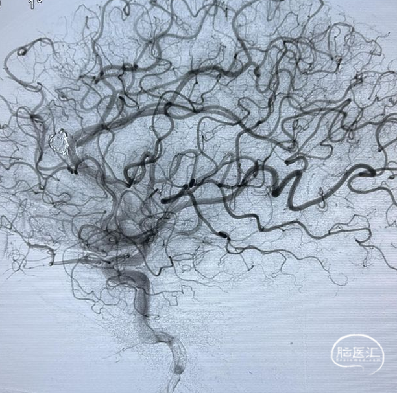

术后影像

术后多角度造影显示动脉瘤致密填塞,其他血管显影正常。术后CT无异常,mRS 0 分。

术后CT未见异常,mRS 0 分,无神经系统症状和体征,计划术后半年后复查DSA